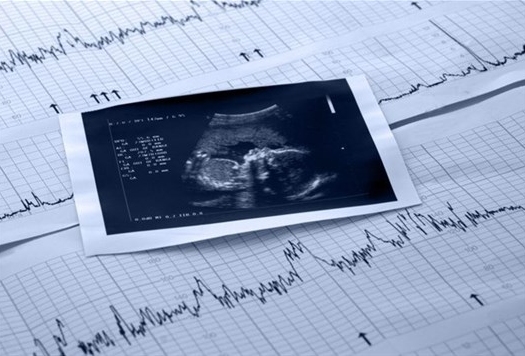

كيف اعرف نبض الجنين بالبيت؟ هناك الكثير من الأمور التي تُثير قلق أي أم في فترة الحمل خاصةً لو كان حملها الأول؛ إذ لا تكون عارفة بالعلامات التي تؤكد لها أن جنينها في صحةٍ وسلامٍ، ولأن النبض من أولى تلك العلامات سوف نوضح هل توجد أشياء تساعد على ظهور نبض الجنين في المنزل.

ترغب الكثيرات من النساء بمعرفة الطرق المنزلية التي تُمكنهن من سماع نبض الأجنة؛ إذ إنهن يعتقدن أن النبض مثل الحركة من المتاح الشعور بكليهما، إلا أن هذا الأمر غير صحيح على الإطلاق؛ ذلك لأن النبض من غير الممكن الشعور به من قِبل الأم في أي مرحلة من مراحل الحمل بالطرق التقليدية.

بل يجب استخدام طرق طبية معينة مثل جهاز السونار وربما السماعة الطبية، وحتى تلك الأخيرة قيل إنه من الصعب سماع نبض الجنين من خلالها خاصةً لو كان الطبيب غير مُتمرس وذا خبرة.

في أي أسبوع يظهر نبض الجنين في السونار

أشار الأطباء إلى أن نبض الجنين من الممكن سماعه بواسطة السونار الطبي بدءًا من الفترة 6 – 7 أسابيع من الحمل، إلا أنه أيضًا في حال اُستخدم السونار المهبلي قد يتمكن الطبيب من سماعه في نهاية الأسبوع الخامس، مع العلم أن الوقت قد يختلف واقعيًا طبقًا لمدى صحة حساب مدة الحمل.

نبض الجنين الطبيعي في التخطيط

بجانب ضرورة عدم المخاطرة بتجربة أيٍ من الوسائل لمعرفة نبض الجنين في المنزل فإن الأجهزة المُستخدمة من قِبل الطبيب هي فقط ما توضح النبض الفعلي للجنين ومن ثم يتم الاطمئنان إذ كان طبيعيًا أم غير ذلك؛ إذ إن المعدل الطبيعي يتراوح بين 110 – 160 نبضة/ دقيقة.

إن العلامات الحيوية للجنين مثل النبض لا يمكن أن تستدل عليها الأم في المنزل، وهذا ما يعني أنه لا غنى أبدًا عن أهمية زيارة الطبيب والكشف بالطرق المخصصة لمعرفته والتأكد من أن الجنين بخير، كذلك تجنبًا لتجربة أي وسيلة قد تُشكل خطرًا على صحة الأم وجنينها.